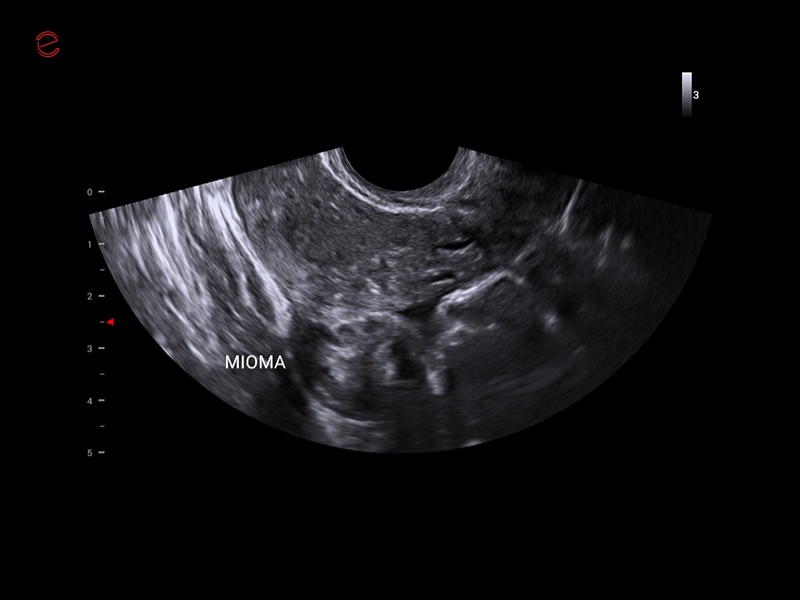

MyLab™X1 Go - WH Mioma

MyLab™X1 Go - WH Mioma